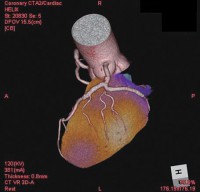

- 図2 PhyZiodynamicsによるmyocardial bridge症例の

Slab MIP表示(CT)

左前下行枝#7にmyocardial bridgeが認められる。心筋の収縮に伴い血管内腔が狭くなる様子が見てとれる。